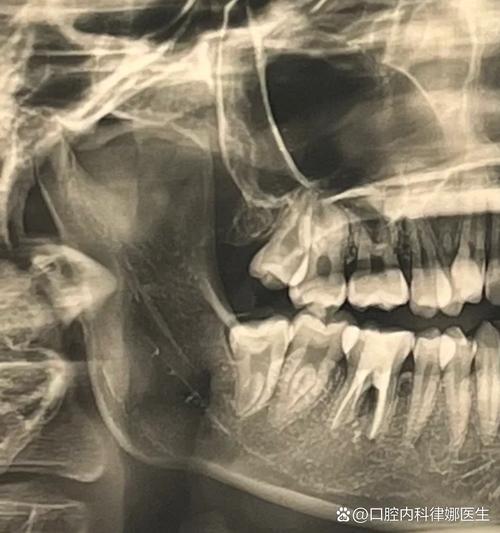

牙槽骨的骨高度、宽度、密度是决定能否植牙及选择何种种植体的核心指标,传统X光片(如根尖片、曲面断层片)是二维影像,存在放大失真、重叠干扰等问题,无法准确测量骨量,下颌骨后区的牙槽骨可能因吸收呈现“倒凹”形态,二维片容易误判骨量充足,实际三维CT才能清晰显示骨缺损区域,避免种植体穿出骨壁。

识别重要解剖结构,规避手术风险

口腔内分布着密集的神经、血管,如下颌的“下牙槽神经管”(内有神经血管束,损伤会导致下唇麻木)、上颌的“上颌窦”(底部与后牙区牙槽骨相邻,穿刺可能引发感染),CT能精准定位这些结构的走行、位置及与牙槽骨的距离,当后牙区骨高度不足5mm时,CT可明确上颌窦底的位置,判断是否需要“上颌窦内提升”或“外提升”手术,避免盲目操作导致上颌窦穿孔。

曲面断层片虽能显示全口牙槽骨,但影像重叠严重,无法区分骨皮质与骨松质,对神经、上颌窦等结构的定位误差可达2-3mm,下颌神经管实际距离牙槽嵴顶5mm,曲面断层片可能显示为7mm,若医生按此数据植入种植体,极易损伤神经,导致下唇麻木。 -